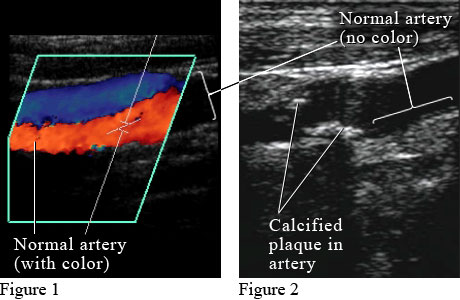

Idaho. Figure 1 shows a color Doppler ultrasound picture of

blood flowing through a normal artery (red) and vein (blue). Figure 2 shows an

ultrasound picture of an artery narrowed by the buildup of calcium and fat

(cholesterol) in the inner lining of the artery, called plaque, which leads to

"hardening of the arteries" (atherosclerosis). ByHealthwise Staff Primary Medical ReviewerKathleen Romito, MD - Family Medicine Specialist Medical ReviewerHoward Schaff, MD - Diagnostic Radiology Current as ofOctober 14, 2016 Current as of: